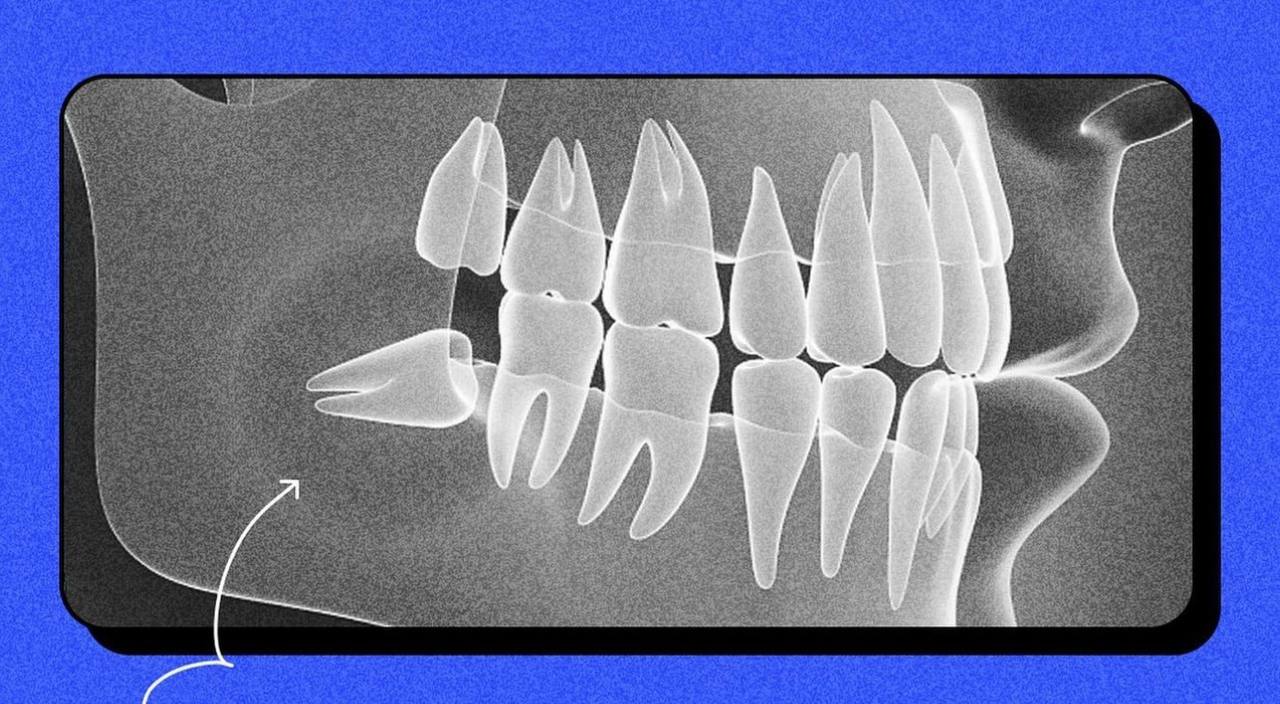

Приклад поганого росту зуба мудрості (скриншот: instagram.com/sviy.doc)

Фахівці кажуть, якщо зуб мудрості виріс рівно, то людині пощастило. Якщо ж зуб виростає криво, то доведеться видаляє два зуби – восьмий і сьомий.